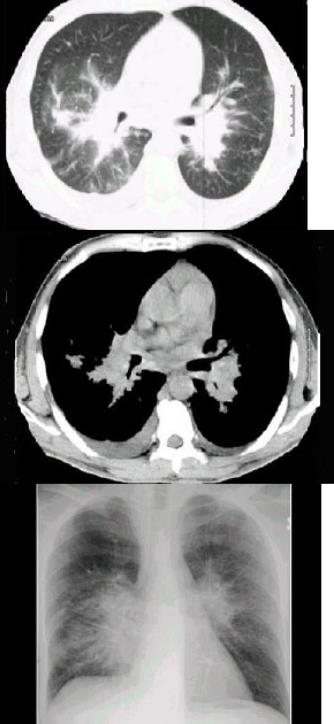

HIV阳性患者近来咳嗽,胸闷,胸片检查发现病变,CT检查如图,最有可能的诊断为()。